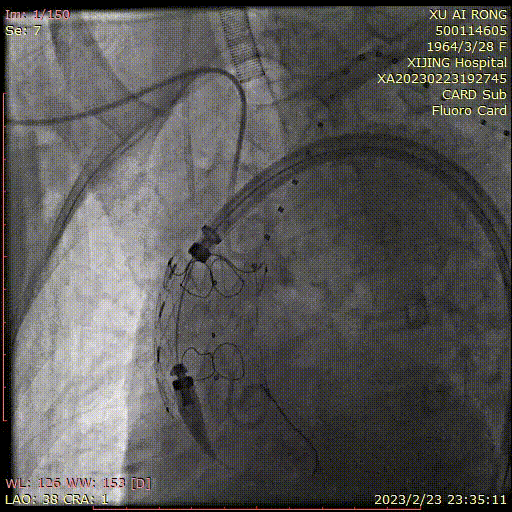

WeFlow-Arch™病例展示

★ 病例1:模块内嵌分支胸主动脉覆膜支架系统

导入近端主体支架

释放近端主体支架

双球囊同时扩张内隧道

释放无名动脉

支架

内扩无名动脉

无名动脉支架

通畅

释放左颈总动脉支架

内扩无名动脉支架

导管置于

左锁骨下动脉近端

栓塞左锁骨下动脉近端